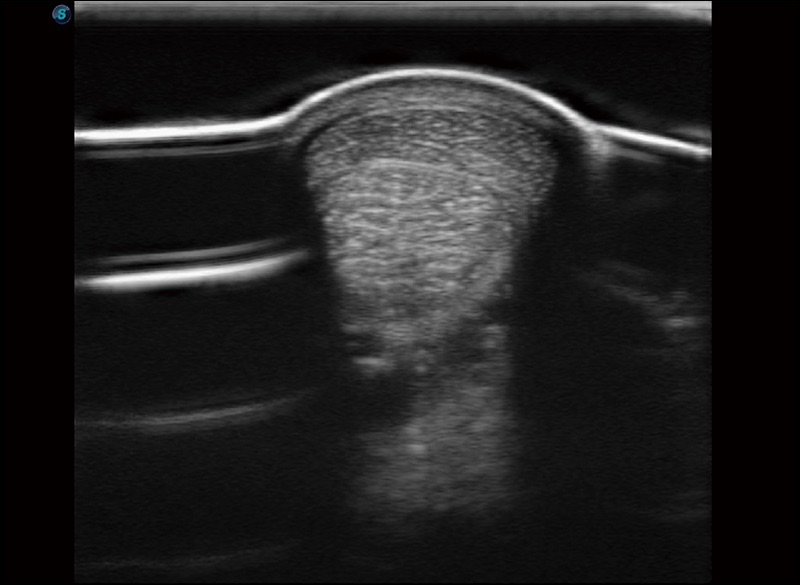

扩展成像

支持线阵和凸阵探头,一键操作即可获得更宽的图像视野